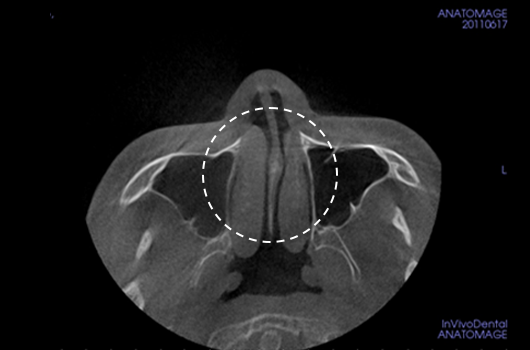

2. Diagnosis of deviated nose and septal deviation

Diagnosis of deviated nose and septal deviation